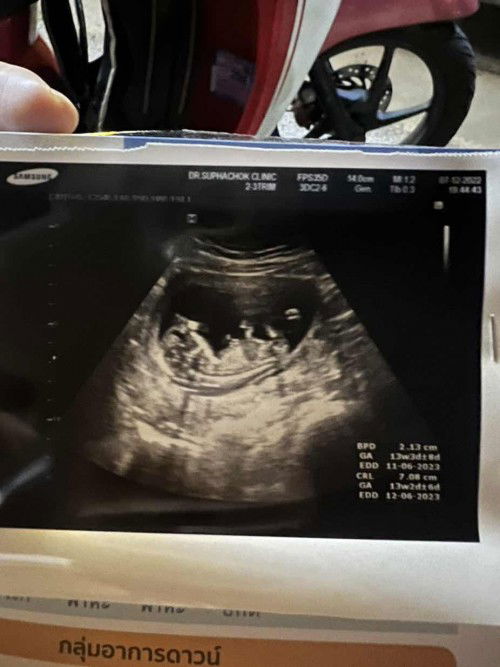

กว่าหนูจะกลับมาอีกครั้ง แม่รอหนูเกือบ 6 เดือน พอหนูมาแล้วพ่อกับแม่ก็เป็นพาหะธารัสซีเมีย แม่ต้องมารอลุ้นฟังผลเลือดอีกว่าหนูจะได้รับผลกระทบมั้ย หากผลเลือดผ่าน ก็มาตรวจ NIPT ลุ้นกลุ่มเสียงดาวน์อีก กว่าจะรู้ผล แม่ใจจะขาดแล้ว ขอให้หนูแข็งแรง ปลอดภัย เรียนรู้และเติบโตไปพร้อมๆกันนะลูก แม่รอดูพัฒนาการและการเจริญเติบโตของหนูทุกวัน #เจ้าความรัก14week